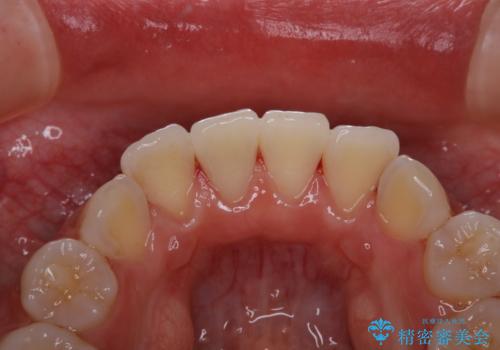

- 子供の頃以来のかなり久しぶりの歯科医院への来院とのことで、プラーク・歯石がべっとり付着していました。

古くからの磨き残しや、歯石などにより、歯肉に炎症がみられ、かなり汚れが多く付着していました。PMTC60分コースで徹底的に汚れをおとしました。施術後の歯肉に出血が見られますが、次第におさまります。